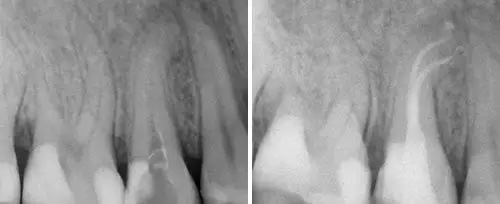

Cavity Preparation